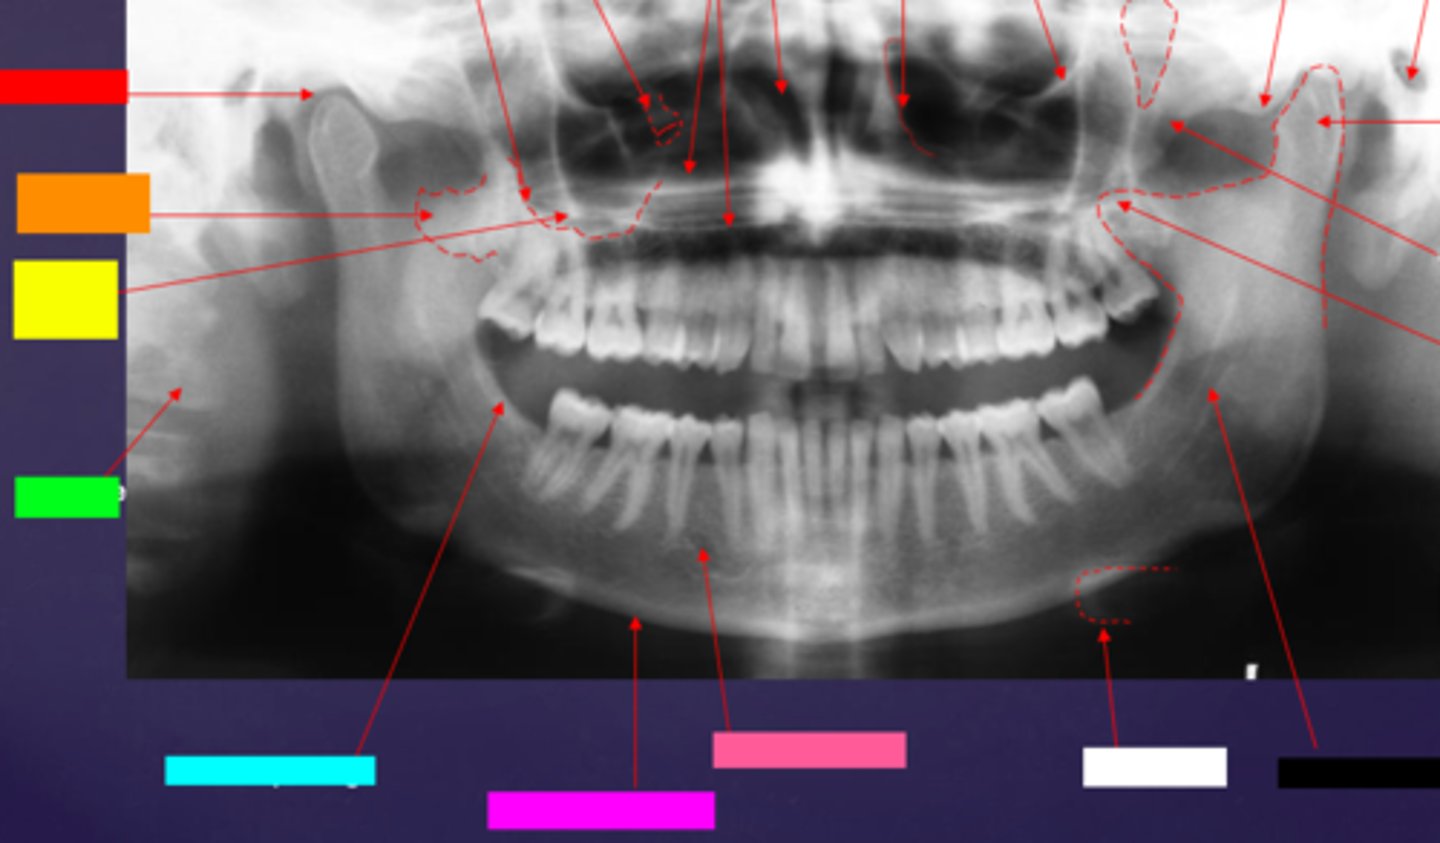

ID the soft tissue anatomy indicated by the arrow pointing from the red box:

posterior pharyngeal wall

ID the soft tissue anatomy indicated by the arrow pointing from the orange box:

soft palate

ID the soft tissue anatomy indicated by the arrow pointing from the yellow box:

dorsal surface of tongue

ID the soft tissue anatomy indicated by the arrow pointing from the green box:

middle nasal meatus

ID the soft tissue anatomy indicated by the arrow pointing from the light blue box:

inferior nasal meatus

ID the soft tissue anatomy indicated by the arrow pointing from the hot pink box:

inferior nasal concha (turbinate)

ID the soft tissue anatomy indicated by the arrow pointing from the brown box:

upper lip

ID the soft tissue anatomy indicated by the arrow pointing from the white box:

lower lip

ID the soft tissue anatomy indicated by the arrow pointing from the grey box:

ghost image of opposite mandible

ala of nose

nasal septum

columna (the septum separating the nostrils)

tragus

ear lobe